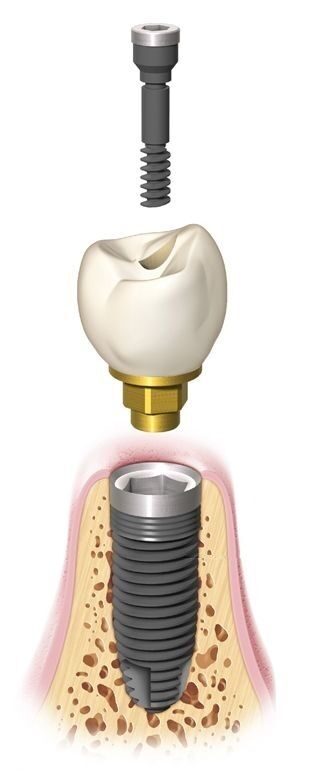

Современные коронки на зубные импланты: виды и фото-примеры